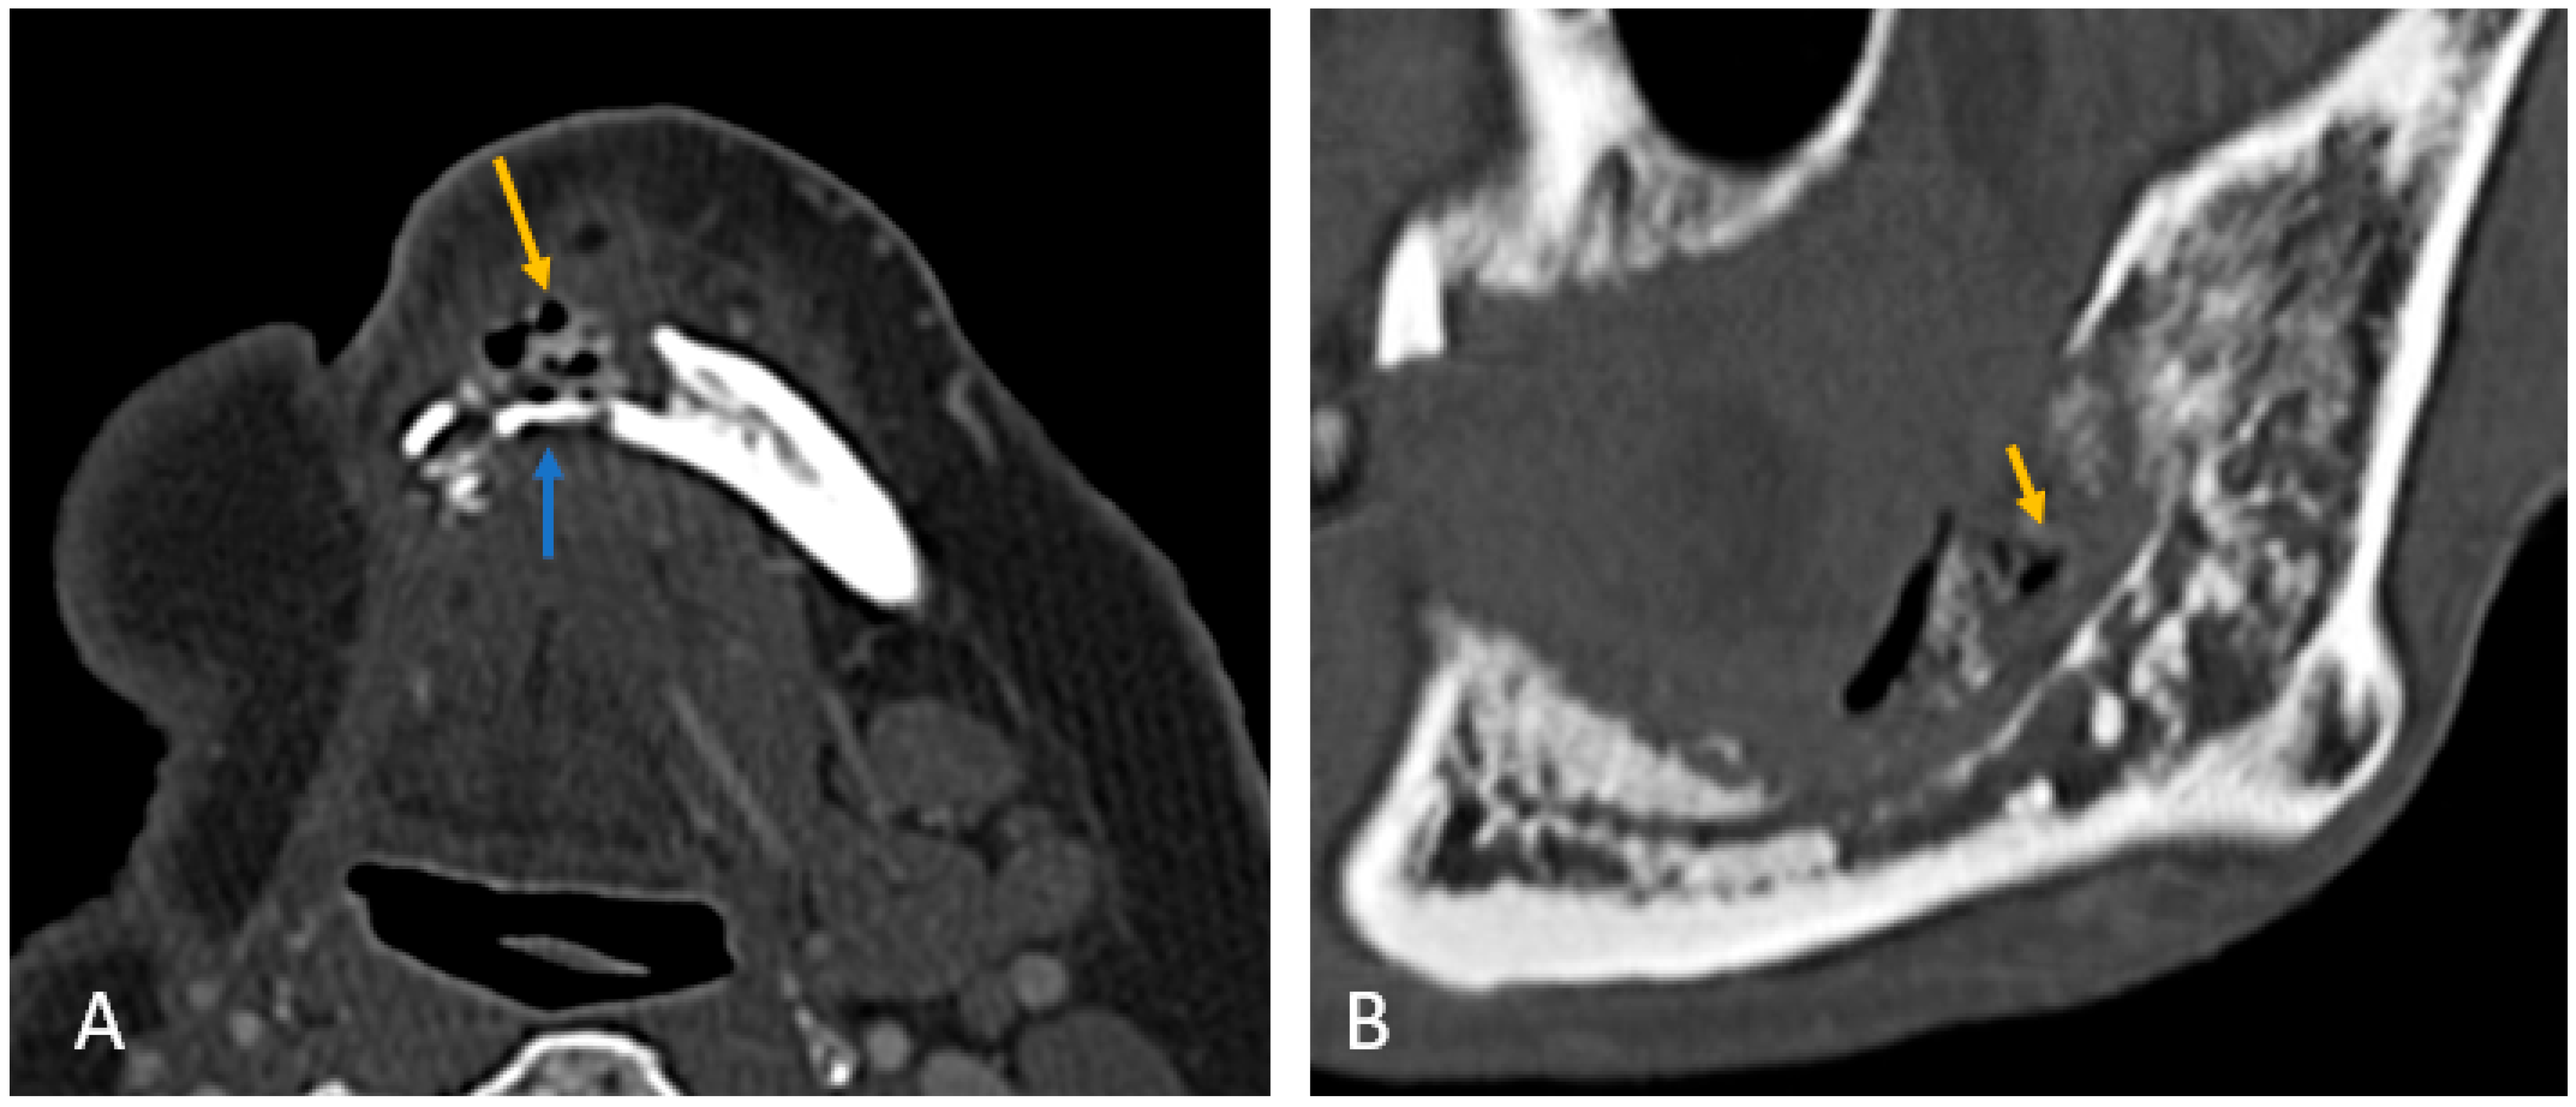

All patients exhibited trabecular and cortical resorption, with resultant bone fragmentation in 83% of cases (Figure 3A–C). Small pieces of bone separated from the main bone were termed as fragmentation (Figure 3A). A dense isolated fragment was termed as sequestration: this was seen in 29% of patients (Figure 3B). Intraosseous gas was seen in six cases as late-stage findings post-fragmentation, and five out of these had sequestration. Sclerosis was observed in 86% (n = 30) of cases and was heterogeneous in 23 cases (77%) and relatively homogeneous in 7 cases (23%). No correlation was found between sclerosis and fragmentation. (Table 1).

Figure 3. Axial CT images showing patterns of bony involvement in ORN. (A) Maximum bone alterations along the lingual cortex (with fragmentation—orange arrow) in a treated case of tongue carcinoma. (B) Maximum changes seen along the buccal cortex in a treated case of buccal carcinoma. (sequestrum—blue arrow). (C) Treated case of carcinoma of the base of tongue with ORN involving the posterior aspect of the body and the angle of the mandible. (D) Treated case of oropharyngeal carcinoma with ORN at both the angles of the mandible and iso-enhancing soft tissue at the site of bony involvement.

In most cases (n = 30; 86%), the site of maximum bone involvement was close to the primary, like the focal ORN at the resected margin, and the pattern of bone involvement was predictive of ORN (Figure 3A–D).

Buccal mucosa/alveolus carcinoma: involvement of the adjacent mandible and ipsilateral maxilla was common, with bone changes predominantly observed at the primary site (Figure 3A).

Segmental mandibulectomy cases exhibited ORN at the cut margin and ipsilateral maxilla, with involvement of the buccal cortex more common than the lingual cortex (Figure 2A):

Anterior tongue carcinoma (Figure 3B) showed isolated diffuse mandibular involvement, with predominant lingual cortex involvement (unlike buccal or alveolar carcinoma).

Oropharyngeal and laryngeal carcinoma (Figure 3C,D): typically involved the angles of the mandible and adjacent posterior body/ ramus with sparing of the remaining mandible.